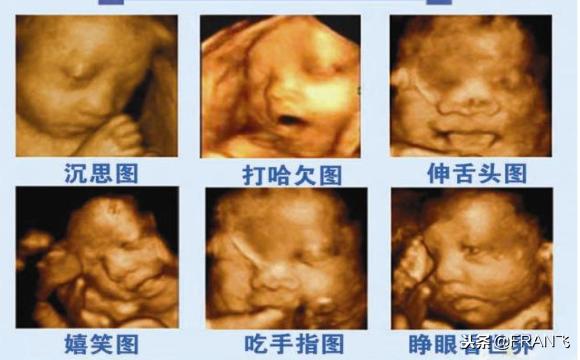

四维彩超能够直观地看到胎儿在母体内的活动状况,根据活动情况来判断胎儿的发育是否良好,一般来说,四维彩超是从胎儿面部畸形、神经系统、消化系统、泌尿系统、其它畸形几个方面来检查的,通过四维彩超,可以检查出来胎儿是否有唇腭裂,是否脑积水、脊柱裂,内脏外翻、肾积水、尿道梗阻、羊水过多等问题。